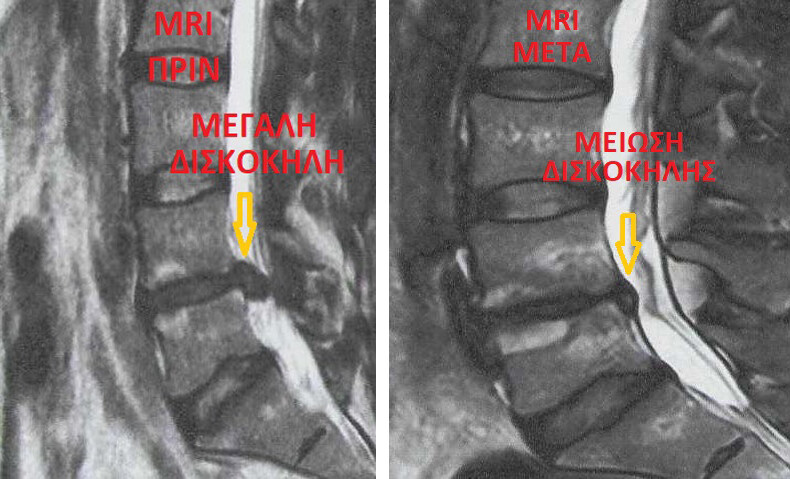

Μια από τις σημαντικότερες εξελίξεις στη χειρουργική θεραπεία των παθήσεων της σπονδυλικής στήλης (δισκοπάθεια, κήλη μεσοσπονδυλίου δίσκου, στένωση κλπ.) που προκαλούν ως επί το πλείστον οσφυαλγία, ισχιαλγία (πόνος στο πόδι), οσφυοϊσχιαλγία, μηραλγία, αυχεναλγία, ραχιαλγία κλπ. είναι η ανάπτυξη της ελάχιστα επεμβατικής χειρουργικής σπονδυλικής στήλης MISS (minimal invasive spine surgery). MISS - Μπενάρδος, 18ος χρόνος 2496 επεμβάσεις.

Ο Ορθοπαιδικός Χειρουργός Σπονδυλικής Στήλης Μπενάρδος Νικόλαος με τη δημιουργία της MISS - Μπενάρδος είναι από τους πρωτεργάτες στην καθιέρωση στην Ελλάδα, της ρομποτικής χειρουργικής σπονδυλικής στήλης (2008 1η ρομποτική διαδερμική σπονδυλοδεσία στην Ελλάδα), ενδοσκοπικής χειρουργικής σπονδυλικής στήλης (2009 1η ενδοσκοπική δισκεκτομή ομάδας MISS - Μπενάρδος) και δισκοπλαστικής με έγχυση ενδοδισκικού τζελ (discogel)

Δισκοπλαστική (Discogel, RF)